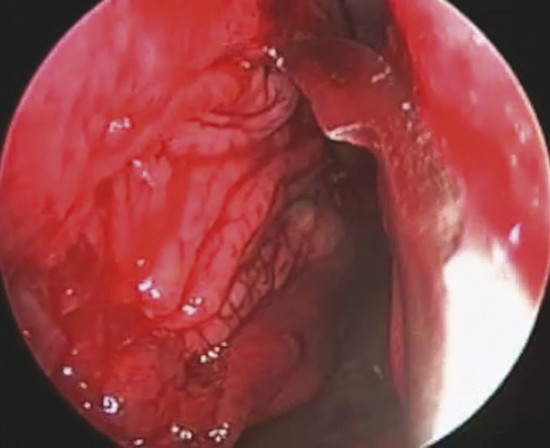

The perforation margins are then bilaterally trimmed and widely detached all around the perforation from the underlying cartilage or bone by a sickle knife to achieve a “refreshening of the edge” (Fig. 19‑1). It is important to elevate bilaterally an area of mucoperiosteum or mucoperichondrium of at least 1 cm all around the perforation.